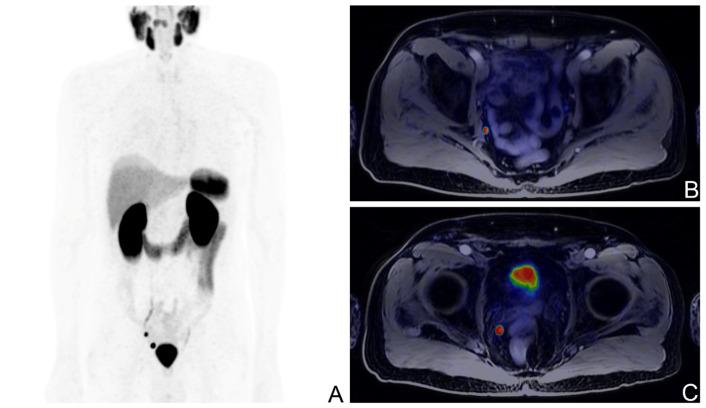

Localized prostate cancer (PCa) can be treated with radical prostatectomy (RP). Up to 30% of patients undergoing this procedure experience biochemical recurrence (BCR), namely the rise in serum prostate-specific antigen (PSA) levels during the post-surgical follow-up, requiring further treatments and with the risk of severe disease progression. Currently, the most accurate imaging technique to confirm, detect, and locate disease relapses in BCR patients is prostate-specific membrane antigen (PSMA)-targeted PET, as recommended by international clinical guidelines. The aim of the study was to investigate potential clinical and pathological predictors of PSMA PET positivity, validated by clinical and instrumental follow-up or histopathological data. In this study, a selected cohort of BCR patients after RP and no other PCa-related therapy who underwent either PSMA PET/CT or PSMA PET/MRI has been analysed. Among the considered predictors, both pathological staging after RP equal or higher than pT3a and higher PSA levels at the time of the scan were significantly correlated with PSMA PET positivity on multivariate logistic regression analysis. As expected, PSMA PET confirmed its role as an accurate imaging technique in the setting of BCR in PCa. These findings may inform appropriate and tailored patient selection and scan timing to optimize and fully exploit this powerful diagnostic tool.

局限性前列腺癌(PCa)可通过根治性前列腺切除术(RP)进行治疗。接受该手术的患者中,高达30%会出现生化复发(BCR),即在术后随访期间血清前列腺特异性抗原(PSA)水平升高,这需要进一步治疗且存在疾病严重进展的风险。目前,国际临床指南推荐,对于BCR患者,确认、检测和定位疾病复发的最准确成像技术是前列腺特异性膜抗原(PSMA)靶向PET。本研究的目的是通过临床和仪器随访或组织病理学数据验证,调查PSMA PET阳性的潜在临床和病理预测因素。在本研究中,分析了一组经过筛选的RP术后且未接受其他PCa相关治疗、接受了PSMA PET/CT或PSMA PET/MRI检查的BCR患者。在考虑的预测因素中,RP术后病理分期等于或高于pT3a以及扫描时较高的PSA水平在多因素逻辑回归分析中均与PSMA PET阳性显著相关。正如预期的那样,PSMA PET证实了其在PCa的BCR情况下作为一种准确成像技术的作用。这些发现可能为适当且个性化的患者选择和扫描时机提供参考,以优化并充分利用这一强大的诊断工具。